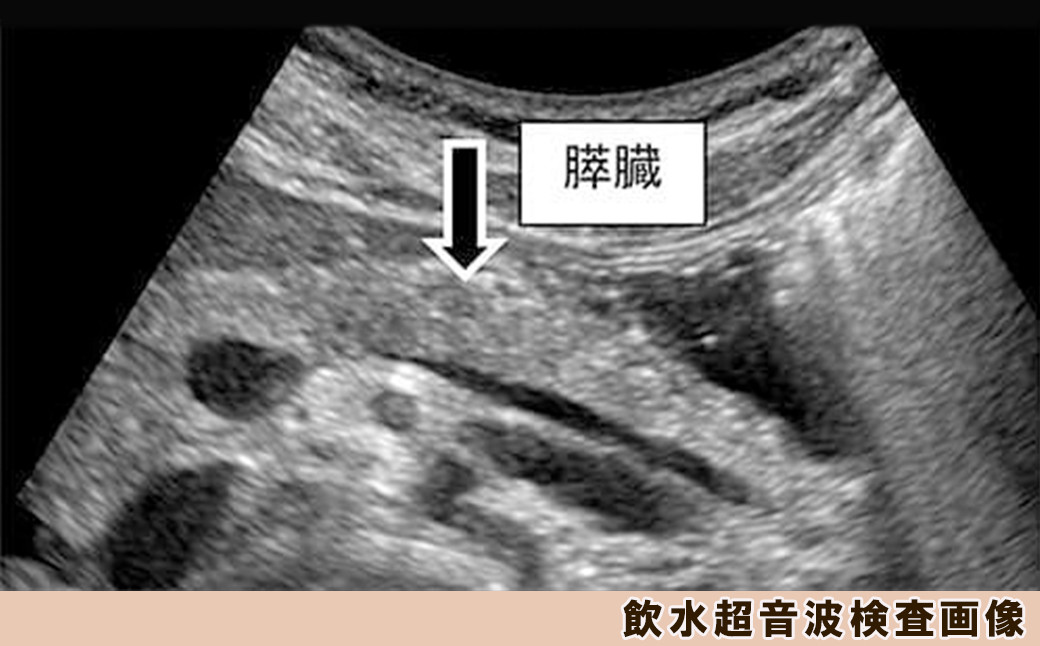

◆飲水超音波検査

飲水することで胃の背側にある膵臓の観察をしやすくし、通常の超音波検査よりも入念に膵臓を観察します。